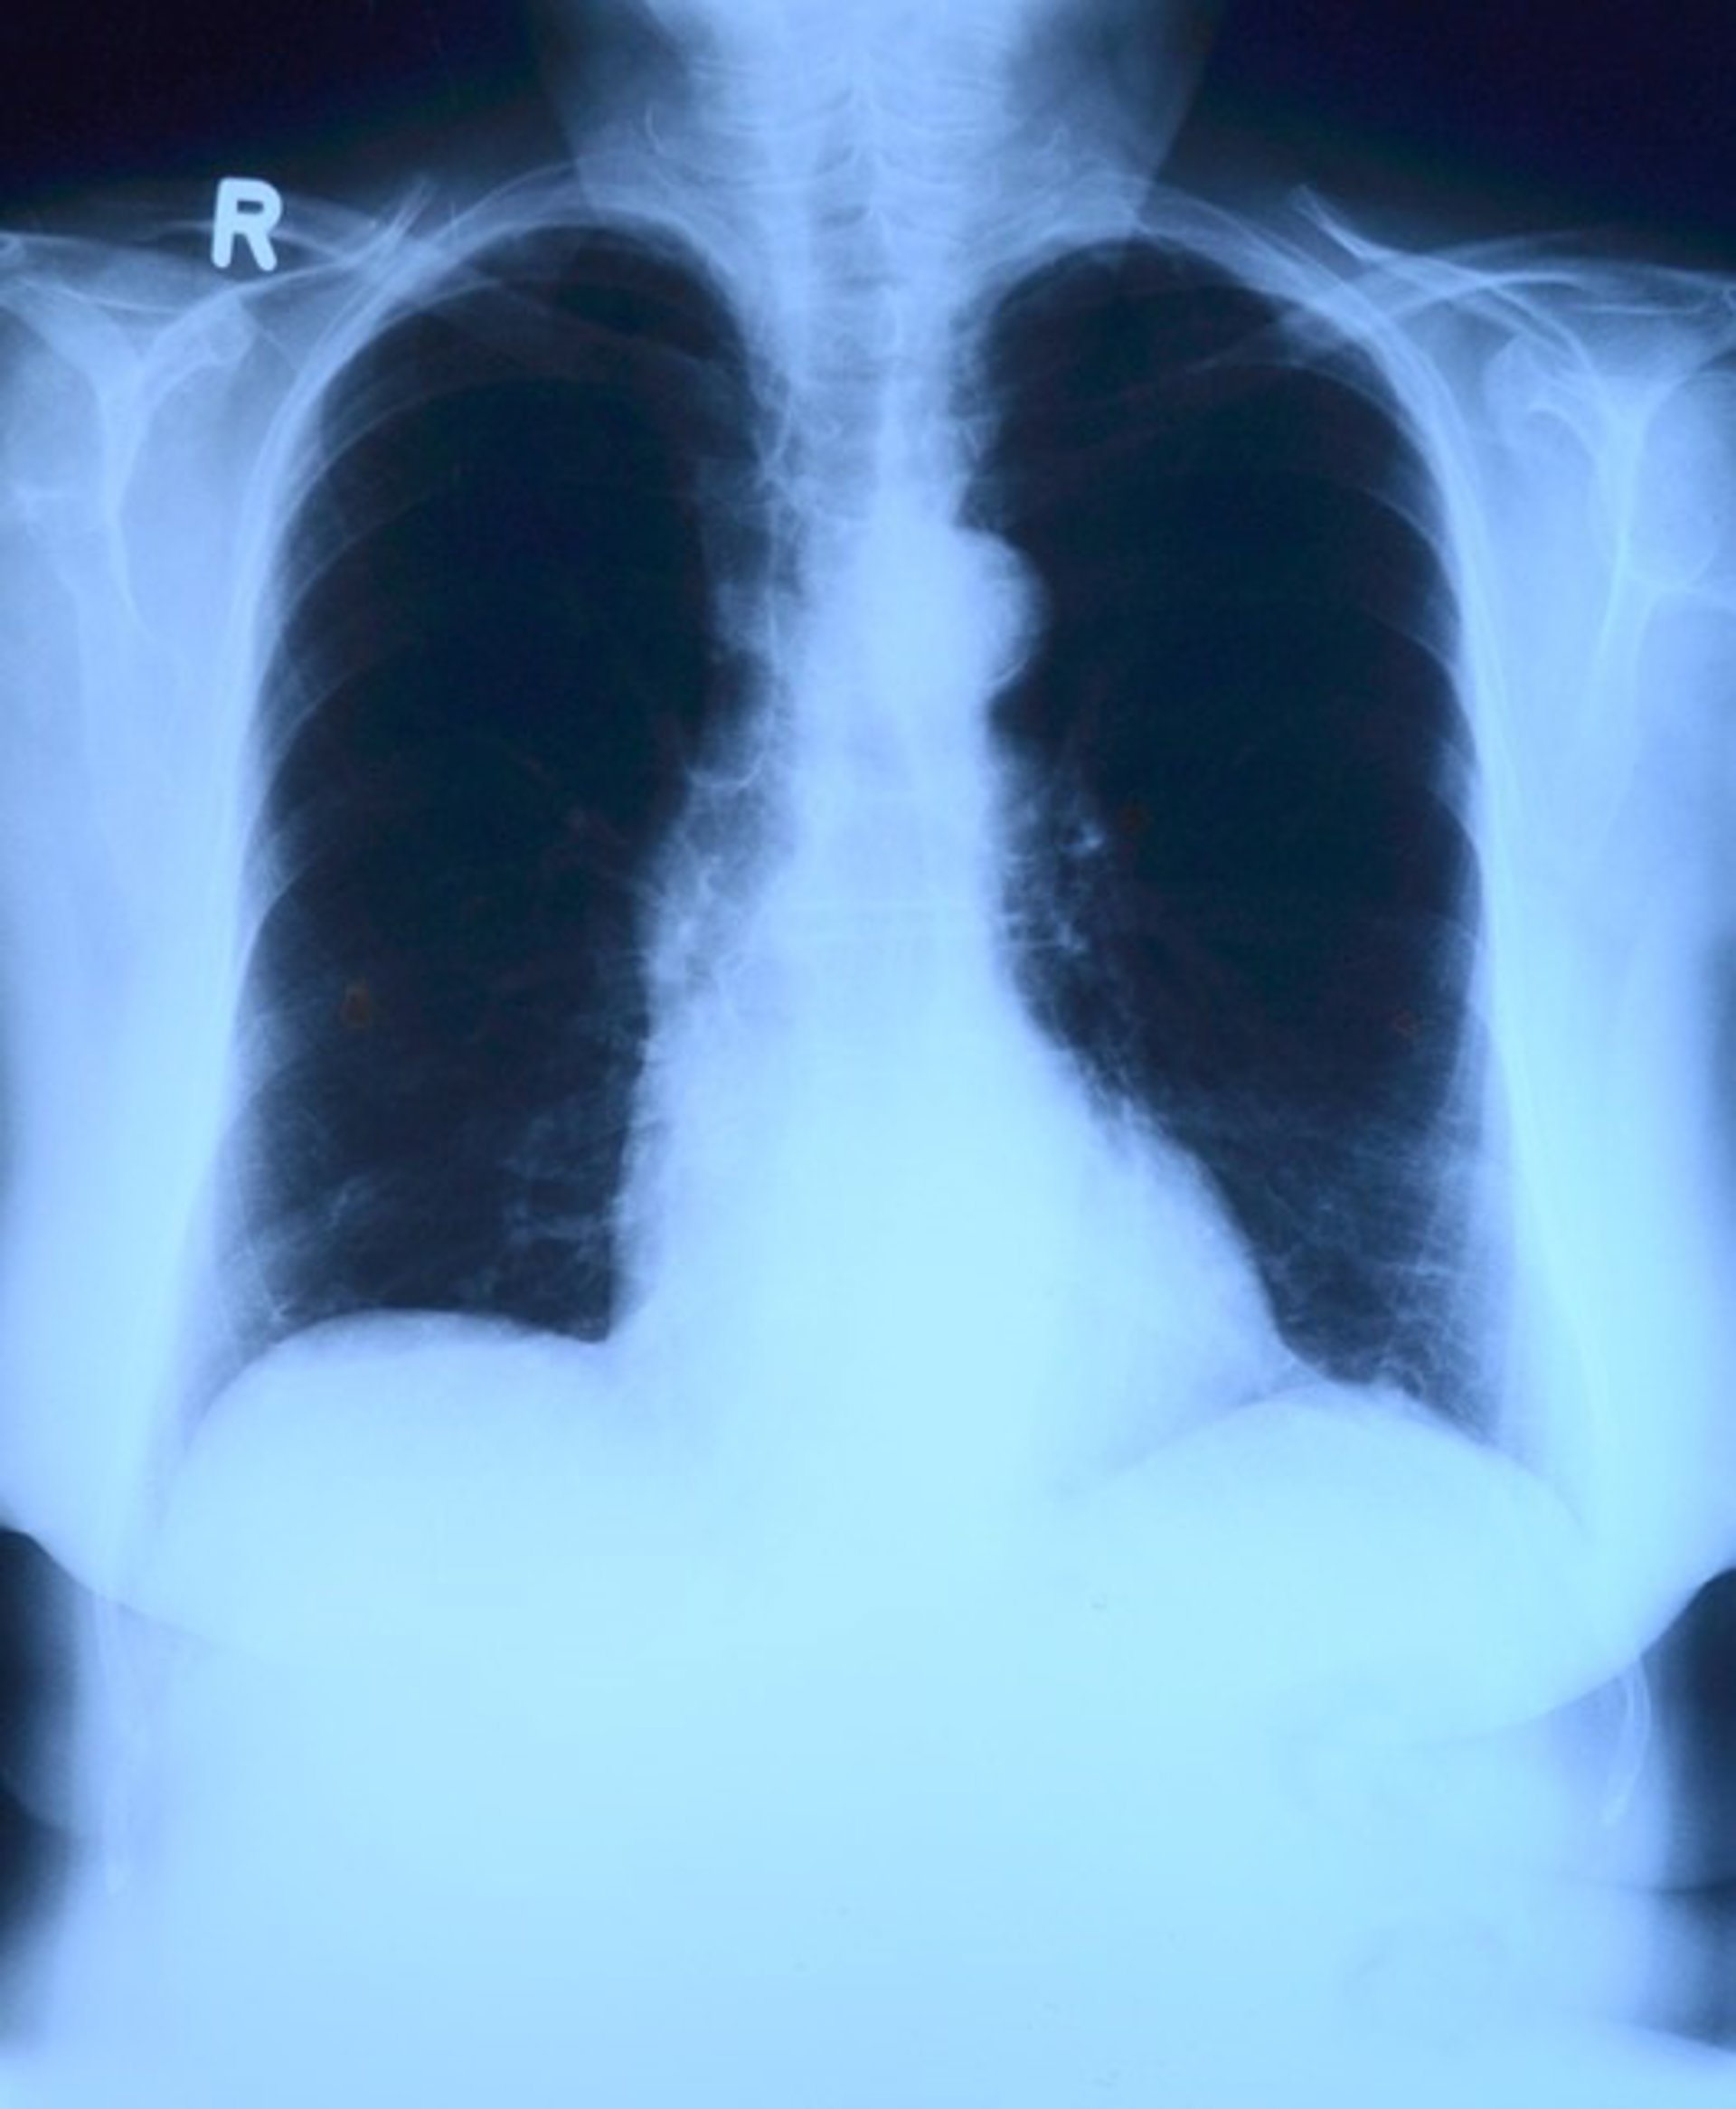

Embargada.- Recuperan pulmones humanos rechazados para trasplante usando una téc - PIXABAY - Archivo

Un equipo multidisciplinario del Centro Médico de la Universidad de Vanderbilt (VUMC) y la Universidad de Columbia, en Estados Unidos, ha demostrado que los pulmones de donantes humanos lesionados que no se pudieron trasplantar pueden recuperarse mediante la circulación cruzada entre el pulmón humano y un huésped xenogénico, es decir, animal.

La nueva técnica, descrita en un estudio publicado en la revista 'Nature Medicine', tiene el potencial de aumentar el suministro de pulmones de donantes disponibles para trasplante, salvando la vida de las personas que de otro modo morirían mientras esperaban en la lista de trasplantes.

Los pulmones son el órgano sólido menos utilizado para el trasplante porque solo el 20% de los pulmones de los donantes se consideran en condiciones suficientes para el trasplante, explica el autor Matthew Bacchetta, profesor asociado de Cirugía Torácica y profesor adjunto asociado de Ingeniería Biomédica en la VUMC.